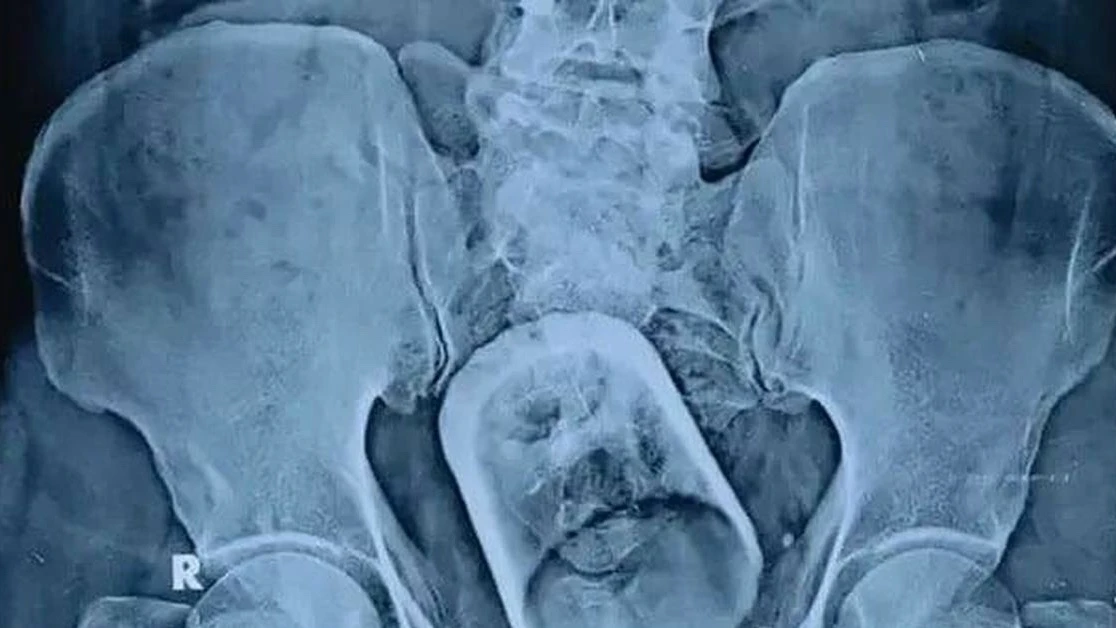

💥💥💥 Невыдуманная история о неотложной помощи в г.Нефтекамск. Обратилась совершенно отчаянная мать. Её сын пяти лет, имеет статус инвалид, родился недоношенным. С малых лет по больницам, мать поддерживает ребенка, все внимание полностью его здоровью. В августе этого года у ребенка диагностировали острый аппендицит, госпитализировали, провели операцию. В течении нескольких дней после - состояние малыша ухудшалось, температура, боли. НО! врачи говорили, что это нормально. Провели УЗИ, на котором обнаружили инородное тело в теле ребенка. 😳 МАТЕРИ ОБ ЭТОМ НЕ СКАЗАЛИ, РЕЗУЛЬТАТ УЗИ НА РУКИ НЕ ДАЛИ и просто сказали - готовьтесь на еще одну операцию. 😧😧😧 Зачем и в связи с чем - дали неоднозначные пояснения, просто СРОЧНО увезли на операцию.

После повторной операции легче не стало. Второй наркоз дался еще сложнее. Ребенку становилось то хуже, то лучше. 🥺🥺🥺

Врачи говорили, что это нормально и несмотря на жалобы матери и ребенка все равно выписали из больницы. Все это время врач с задумчивым лицом приходил, смотрел и уходил. Не ставя диагноза - почему же была повторная операция, почему сейчас не стало лучше. 😬😬 На вопросы не отвечал.

Отчаянная мать видя состояние сына обратилась за помощью в платную клинику г. Ижевск. Там сделали УЗИ, осмотрели ребенка и экстренно госпитализировали на еще одну операцию. Так, менее чем за 2 месяца такой маленький малыш перенес 3 операции! 😢

На УЗИ оказалось, что инородный предмет - марлевая турунда до сих пор находится в теле ребенка! 😨

Получается она была изначально после первой операции и что же тогда они делали на второй операции ?

Стоит также отметить способы послеоперационной обработки раны! После первой и второй операции медсестра на живую раскрывала рану и под кожей терла марлями по открытой ране! Мать при этом в перевязочную не впускали. Ребенок истошно орал на всю больницу - но им было все равно.

После качественной операции в г. Ижевск состояние улучшилось, гной больше не выделялся из раны, она зажила.

Потратив не малые средства на операцию и госпитализацию ребенка мы обратились с претензией в ГБУЗ НЕФТЕКАМСК, подали жалобу в Роспотребнадзор, прокуратуру, ОМВД, Минздрав РБ.

Что интересно, сейчас они пытаются свалить всю вину медучереждения на детскую больницу, якобы на медсестру, которая делала внешнюю обработку раны, когда из нее в больших количествах выделялся гной. Вопрос - как же марля могла попасть в зашитую рану?

Главный врач с нами встречаться не захотел, с нами связался лишь не понятный сотрудник больницы, который грубым образом предложил компенсировать небольшую сумму из потраченных и заключить мировое соглашение в соответствии с которым мы обязуемся не обращаться в суд и забыть что с нами произошло. 😑

При этом Главный врач отчитался перед Минздравом о том, что встреча с ним была назначена, но мы сами не пришли. 🧐

В итоге: ведомственные службы несмотря на все обращения бездействуют.

‼‼‼❤ Считаю, что хватит мириться с такой медицинской помощью в г.Нефтекамск! Друзья, знаю, что почти у каждого жителя города есть страшная история взаимодействия с нашей ГБУЗ. Чтобы наш голос был услышан - нужно составить по каждому случаю обращение-претензию и бороться с ненадлежащим оказанием медицинских услуг. Из-за того, что никто не обращается с жалобами - в Минздраве РБ и выше думают, что у нас в городе все идеально.

Если мы начнем писать, звонить, подавать заявления - качестве медицинских услуг улучшится и мы станем жить лучше. ‼‼‼‼

Если Вы столкнулись с некачественной медицинской помощью прошу обращаться за консультацией! 89631314600